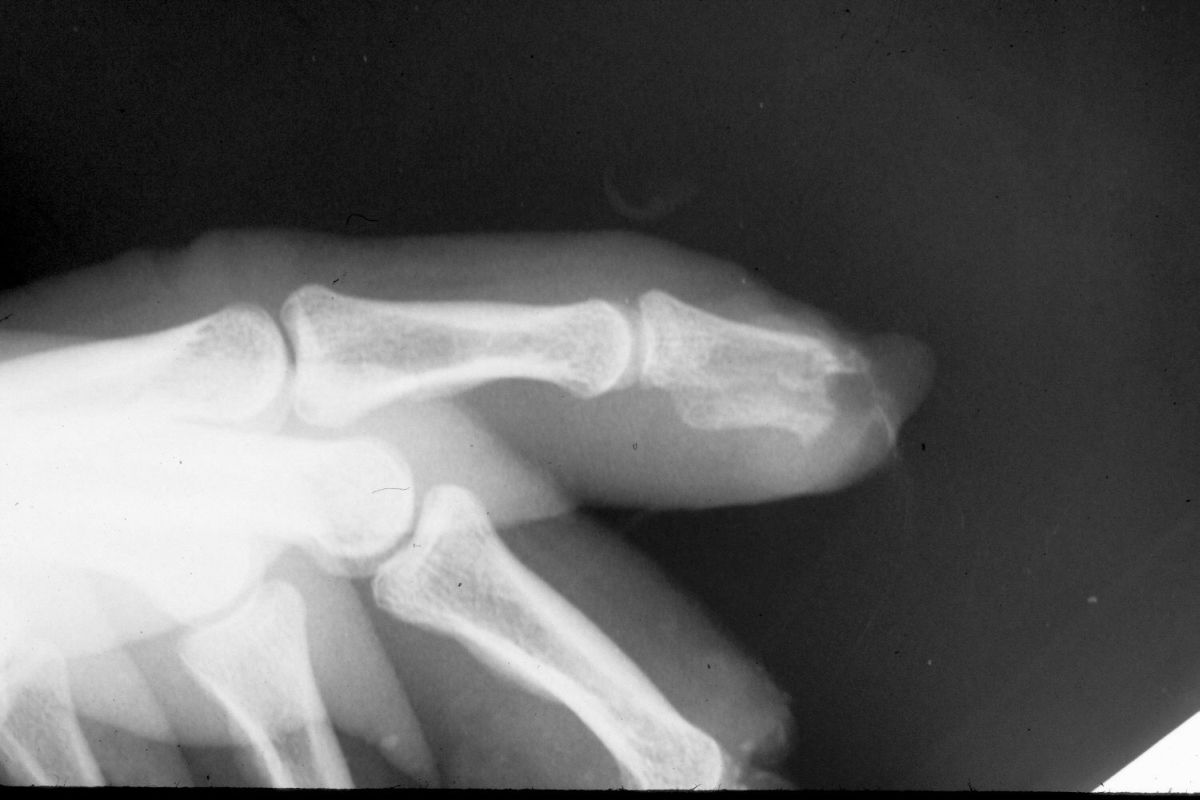

| Case

3. This gentleman sustained partial amputations of all fingers in an industrial press. His index finger was the only digit with a potentially salvageable fingertip. |

| Distal phalanx

fracture stabilization. Pins were placed to protrude

proximally in anticipation of flap cover. |